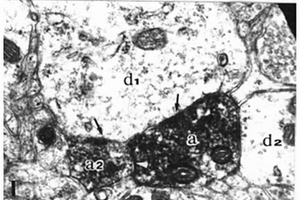

本发明属于细胞染色以及试剂盒的技术领域,具体涉及一种HDN染色液及其用于辣根过氧化酶特异性显色的试剂盒。所述试剂盒包括HDN染色液,所述HDN染色液包括双氧水、缓冲液、硫酸镍铵、3,3’二氨基联苯胺以及氯化铵;所述试剂盒的免疫组织化学的方法如下:1)取被检活性组织切片,固定;2)用一抗检测欲发现的抗原或抗体;3)染色:将所得组织切片浸入HDN染色液中,待组织切片的阳性检测物呈现深紫蓝色;4)清洗组织切片;5)封片,观察组织切片。采用HDN染色液进行染色,得到的试剂盒的敏感度相比常法高10倍以上,可以显示常法染不出的物质,可以减少假阴性结果,避免漏诊。非阳性物质不染色,可以避免假阳性结果。

免疫组织阳性细胞和阴性细胞识别方法

本发明公开了一种免疫组织阳性细胞和阴性细胞识别方法,本发明根据待处理免疫组织化学图像数据本身的最大类间方差方法自适应地确定相应阈值而不是使用固定的阈值,能适应图像在颜色及亮度上的偏差,相比现有方法更稳健;当判别细胞核的阳性、阴性时,将免疫组织化学图像的染色处理信息作为先验信息加以利用,而不需要进行人工标记,避免人为主观因素介入,实现了全自动化处理,提高了分析效率和处理质量的稳定性。